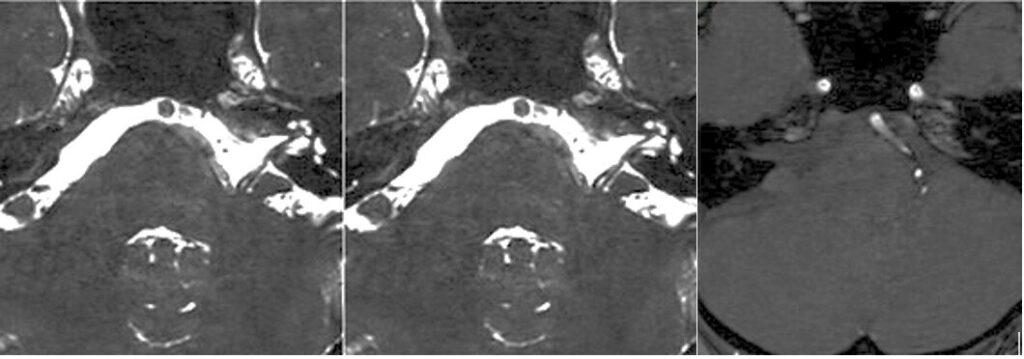

2603月 58歳女性の左顔面痙攣を治療しました。VAとAICAの複合型圧迫でしたがうまく治癒できました。